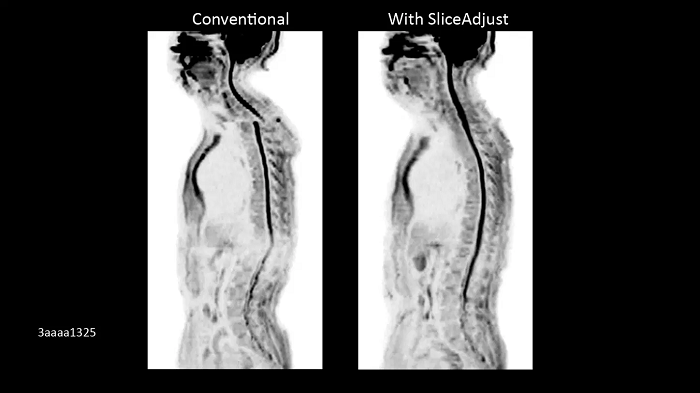

BioMatrix SliceAdjust

Prevent broken spine artifacts in the whole spine DWI

Image Credit: Siemens Healthineers

Enhanced whole-body DWI quality due to BioMatrix SliceAdjust.